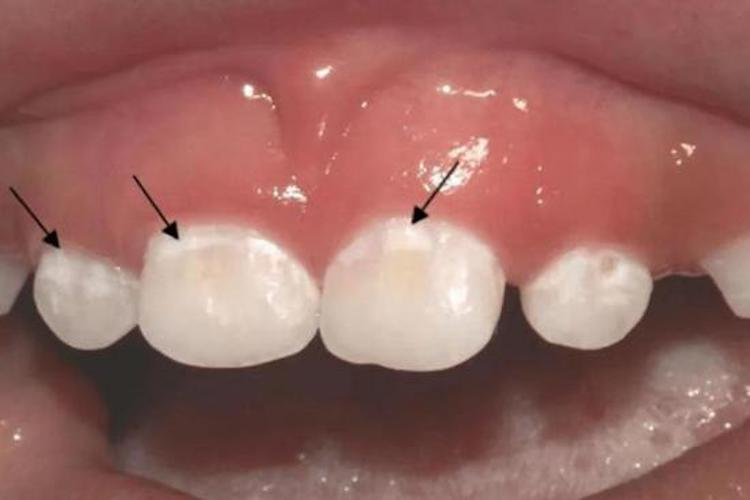

吃糖导致蛀牙牙齿脱矿

糖吃多了可能会导致蛀牙。由于糖含有很多的蔗糖成分,会引起菌斑微生物的堆积、黏附,特别是链球菌以及牙龈卟啉单胞菌。这些细菌沉积在牙釉质上并且会逐渐产酸,腐蚀牙釉质。经过反复腐蚀,逐渐导致牙釉质的晶体结构出现相应的破裂、破坏,蛀牙即可逐渐形成。

如果吃糖后没有及时地刷牙、漱口,这些糖分可能会促进蛀牙的形成,从而使更多的牙齿被破坏。所以,为了预防蛀牙,患者首先要管理好口腔卫生,尽量不要有软垢,不要附着致病微生物。要坚持早晚刷牙、保持口腔健康,尽量少吃甜食,减少蛀牙的发生率。